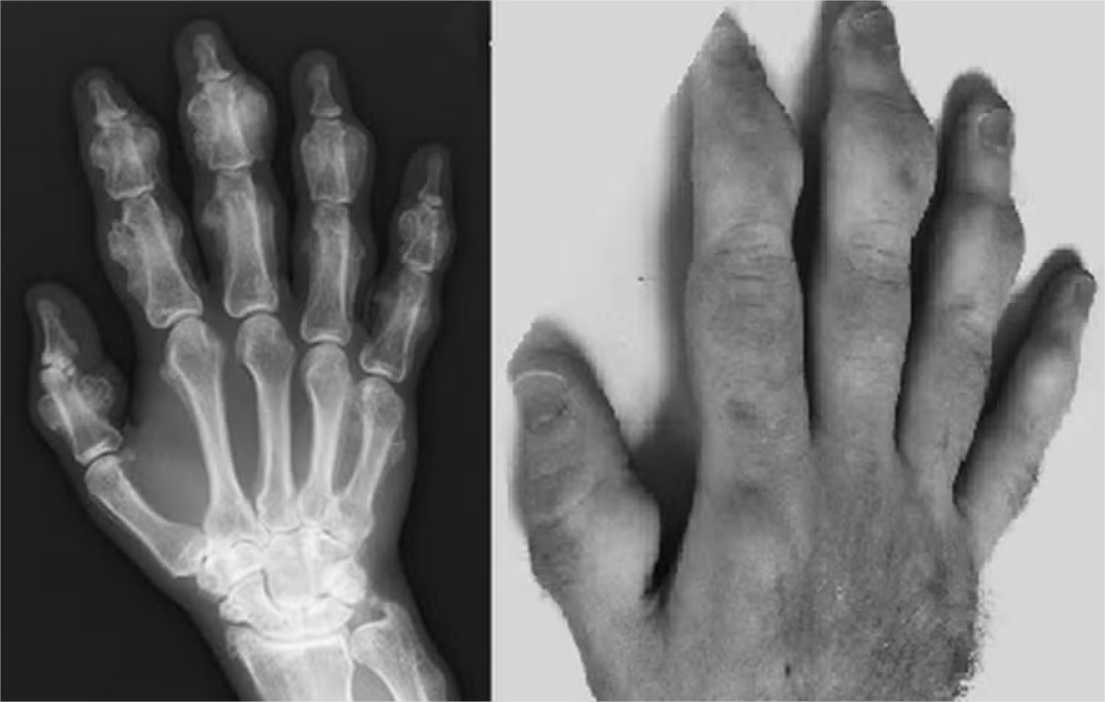

Segundo o site Live Science, que relembrou o caso nesta quarta-feira (22), logo que o paciente foi internado, os médicos notaram que as massas ósseas de seus membros haviam mudado e, com isso, seus dedos tinham, de fato, expandido. A constatação serviu para explicar a postura curvada do homem e a sua dificuldade em andar ou mover seus braços normalmente.

De acordo com o National Institutes of Health (NIH), uma autoridade de saúde dos EUA, os efeitos colaterais da condição são uma combinação de osteosclerose (endurecimento do osso), osteomalacia (desmineralização) e osteoporose (perda de massa óssea) de vários graus. Alguns casos podem ser tão graves, que ainda evoluem para exostose (crescimentos ósseos anormais) e lesões.